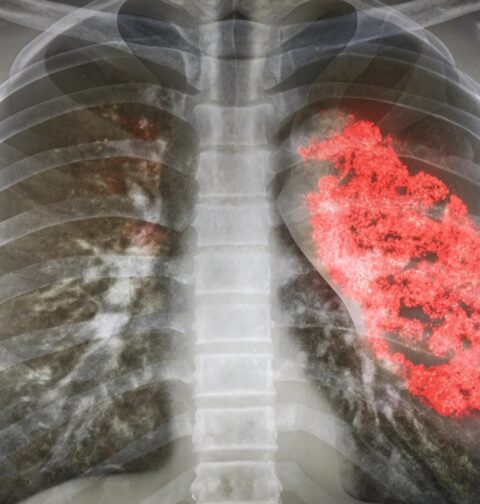

Astăzi, 24 februarie, când în tradiția românească se sărbătorește Dragobetele, vorbim despre „fluturii din stomac” și din perspectivă medicală. Iubirea.